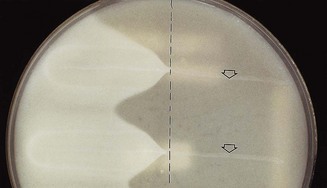

Nagler’s reaction

The neutralization of the α-toxin of the organism growing on agar plates by a specific antitoxin is useful in identification. In this test, the organism is streaked on an agar plate containing egg yolk (which contains high concentrations of phospholipase), half of the plate having been spread with antitoxin; an opaque reaction develops, surrounding the growth of C. welchii in the untreated half of the plate, while in the other half, no such reaction occurs as the toxin is neutralized by the antitoxin (Fig. 13.3).

Fig. 13.3 Nagler’s reaction: when Clostridium welchii is grown in a medium containing egg yolk (lecithin), the enzyme (lecithinase) activity can be detected as opacity around the line of growth. On the right of the plate, no opacity develops, as antitoxin previously applied to this half of the plate has neutralized the toxin. A positive control (top arrow) and a test sample, which is also positive (bottom), are shown.